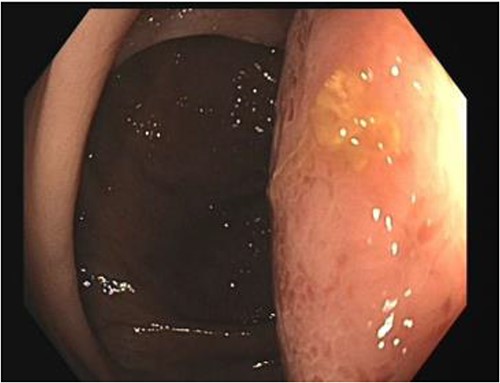

His white cell count was 12.7 × 109/L (reference range 3.7–9.5 × 109/L) and c-reactive protein was 39 mg/L (reference range ≤ 4 mg/L). Hydatid and entamoeba serologies were negative. Carcinoembryonic antigen was elevated to 11.4 ug/L (reference range ≤ 3 ug/L). Abdominal ultrasound showed an uncharacterizable RLQ cystic structure with calcification (Fig. 1). Subsequent computed tomography (CT) scan demonstrated a 56 mm × 43 mm × 58 mm ovoid ascending colon mass with central low density and rim enhancement (Fig. 2). Ileocolic lymphadenopathy up to 7.5 mm in diameter was noted with no evidence of distant metastatic disease.

Ultrasound image demonstrating a cystic lesion with internal calcification and no hypervascularity.

Diagnosis of colonic duplication cyst is reliant on radiology, intra-operative findings and histopathology. The typical finding on ultrasonography (US) is a cystic lesion with hypoechoic outer rim representing the smooth muscle layer [3, 7]. Endoscopic US may additionally demonstrate submucosa and mucosa as inner hyperechoic layers [3, 7]. CT typically demonstrates a fluid filled cystic lesion or a thin walled tubular structure. As in this case, a CT scan with oral contrast may be utilized to evaluate for bowel obstruction.